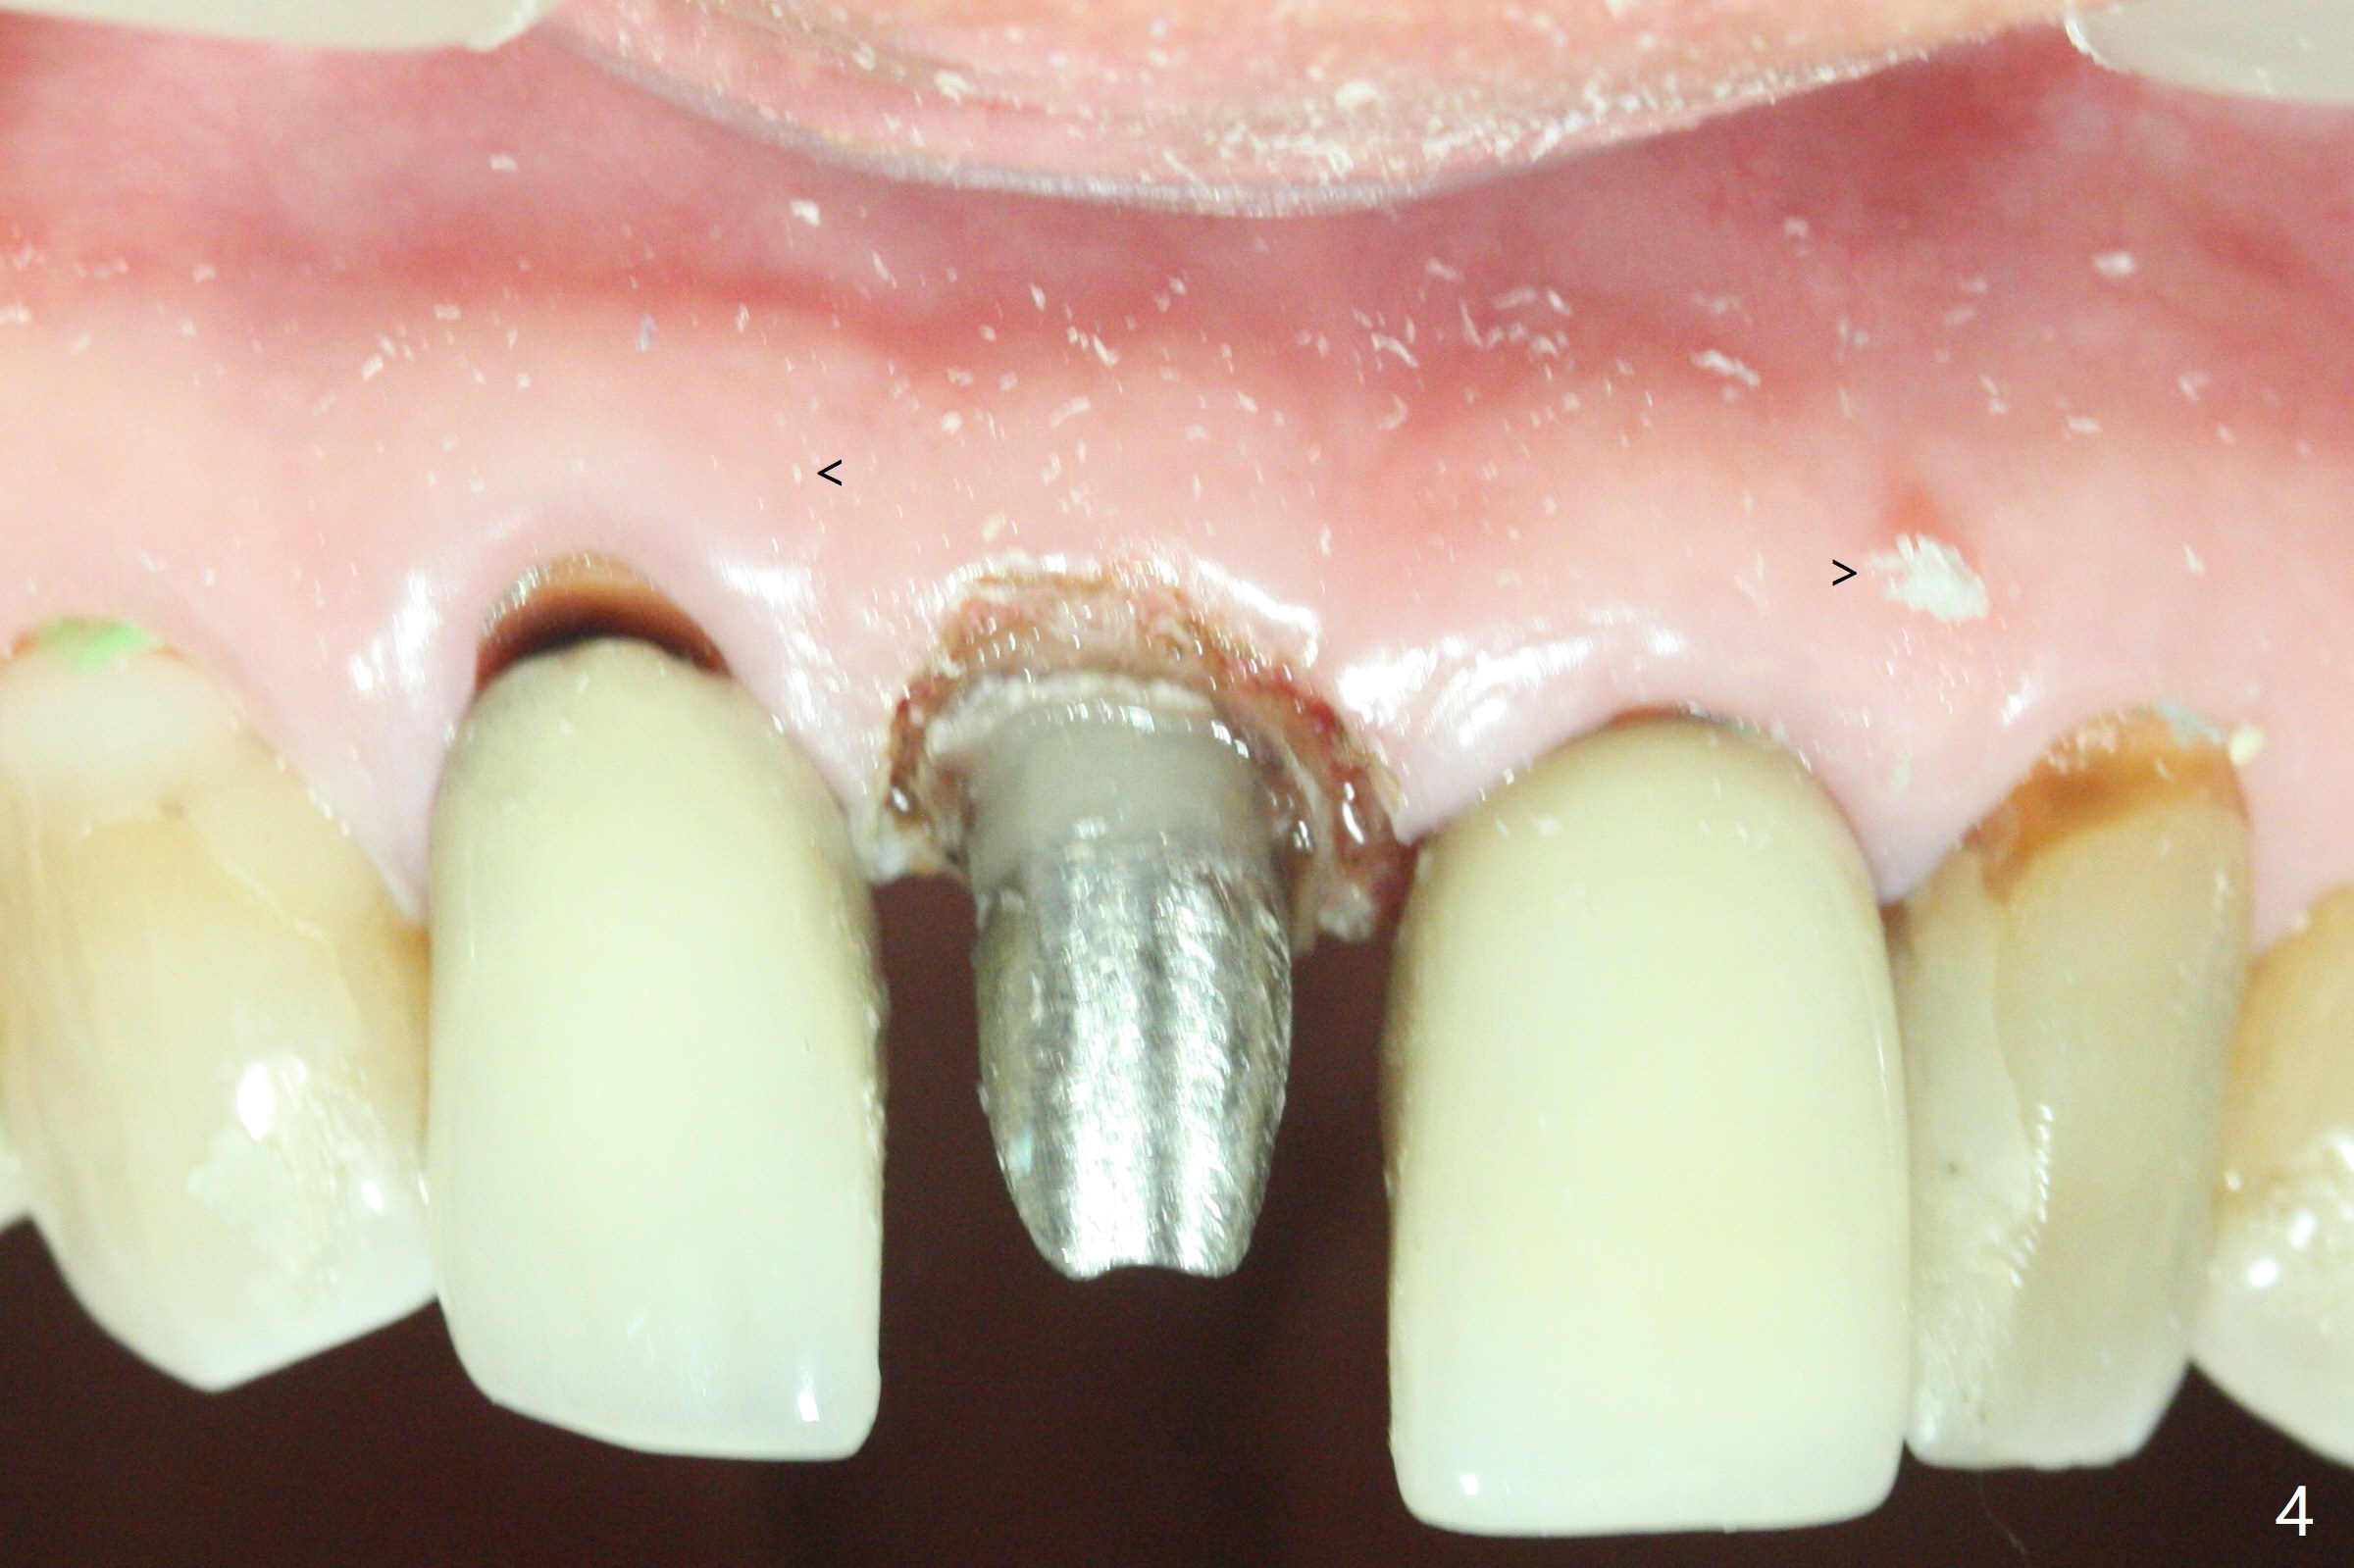

A 66-year-old man returns to clinic for #8 crown redo because of marginal leakage (Fig.1 *). After crown and caries removal, the tooth requires crown lengthening or basically non salvageable (Fig.2,3). For untold reasons, gingivectomy is performed with Waterlase without topical or local anesthesia. Hemostasis is excellent for impression, although there is wide spread of tissue debris from laser (Fig.4 >). The gingiva heals 4 weeks (Fig.5) and 6 weeks (Fig.6) postop.